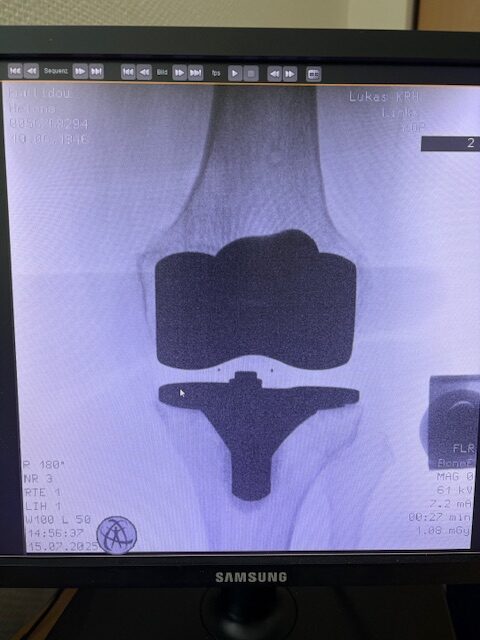

Η επέμβαση πραγματοποιήθηκε με ρομποτικά υποβοηθούμενη τεχνική, κατά την οποία το ρομποτικό σύστημα με καθοδήγησε με ακρίβεια χιλιοστού σε κάθε στάδιο.

Έτσι εξασφαλίστηκε η ιδανική τοποθέτηση των εμφυτευμάτων, η αποκατάσταση του μηχανικού άξονα και η διατήρηση των μαλακών ιστών.

Τα εμφυτεύματα που χρησιμοποιήθηκαν στο γόνατο της ασθενούς είναι της Aesculap: E-Motion Pro, μηριαίο μέγεθος 4, κνημιαίο μέγεθος 4, με ενθέμα (inlay) 10mm.

Η ασθενής κινητοποιήθηκε την ίδια ημέρα μετά την επέμβαση και εξήλθε από το νοσοκομείο την πέμπτη μετεγχειρητική ημέρα.

Ήδη από τις πρώτες εβδομάδες, περπατούσε χωρίς πόνο, με βελτιωμένο εύρος κίνησης.   Η παθητική κίνηση κατα την έξοδο της ασθενούς από την κλινική ήταν E/F : 0-0-120 Επίσης πλήρη σταθερότητα του γόνατος σε κάμψη και έκταση.

Η ακρίβεια του ρομποτικού σχεδιασμού οδήγησε σε άριστη ευθυγράμμιση και φυσική κίνηση, επιτρέποντάς της να επιστρέψει γρήγορα στις καθημερινές της δραστηριότητες και να απολαμβάνει ξανά ποιότητα ζωής και ελευθερία κίνησης!!!